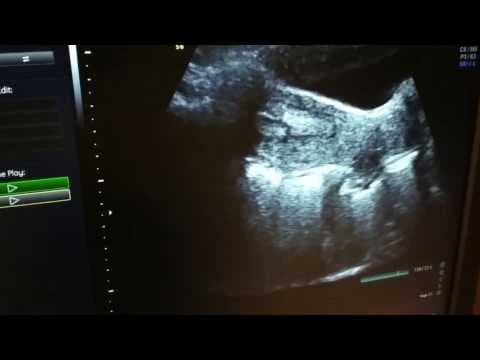

Antralni folikuli su mali folikuli u jajniku koji se mogu prikazati transvaginalnim ultrazvukom, najčešće u ranoj folikularnoj fazi ciklusa. Njihov broj daje uvid u funkcionalnu ovarijsku rezervu, odnosno u to koliko jajnik još raspolaže folikularnim potencijalom za odgovor na gonadotropinsku stimulaciju.

Jedna od njegovih najvećih prednosti jest to što odmah daje i morfološku i funkcionalnu informaciju. Osim samog broja antralnih folikula, istodobno se mogu procijeniti izgled jajnika, volumen jajnika, eventualna prisutnost endometrioma ili drugih cističnih promjena te indirektni znakovi policistične ovarijske morfologije.

To znači da je ultrazvuk više od laboratorijskog markera. On spaja dijagnostiku i planiranje terapije u istom pregledu, što ga i danas čini iznimno praktičnim u pripremi za IVF.